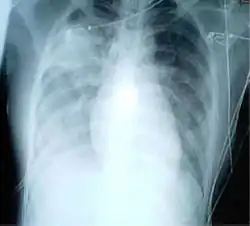

![]() | |

| Chest X-ray of a pneumonia caused by influenza and Haemophilus influenzae, with patchy consolidations, mainly in the right upper lobe (arrow) | |

A chest radiograph is frequently used in diagnosis.[23] In people with mild disease, imaging is needed only in those with potential complications, those not having improved with treatment, or those in which the cause is uncertain.[23][69] If a person is sufficiently sick to require hospitalization, a chest radiograph is recommended.[69] Findings do not always match the severity of disease and do not reliably separate between bacterial and viral infection.[23]

X-ray presentations of pneumonia may be classified as lobar pneumonia, bronchopneumonia, lobular pneumonia, and interstitial pneumonia.[75] Bacterial, community-acquired pneumonia classically show lung consolidation of one lung segmental lobe, which is known as lobar pneumonia.[42] However, findings may vary, and other patterns are common in other types of pneumonia.[42] Aspiration pneumonia may present with bilateral opacities primarily in the bases of the lungs and on the right side.[42] Radiographs of viral pneumonia may appear normal, appear hyper-inflated, have bilateral patchy areas, or present similar to bacterial pneumonia with lobar consolidation.[42] Radiologic findings may not be present in the early stages of the disease, especially in the presence of dehydration, or may be difficult to interpret in the obese or those with a history of lung disease.[24] Complications such as pleural effusion may also be found on chest radiographs. Laterolateral chest radiographs can increase the diagnostic accuracy of lung consolidation and pleural effusion.[41]